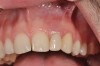

(25.) Preoperative view.

Figure 25